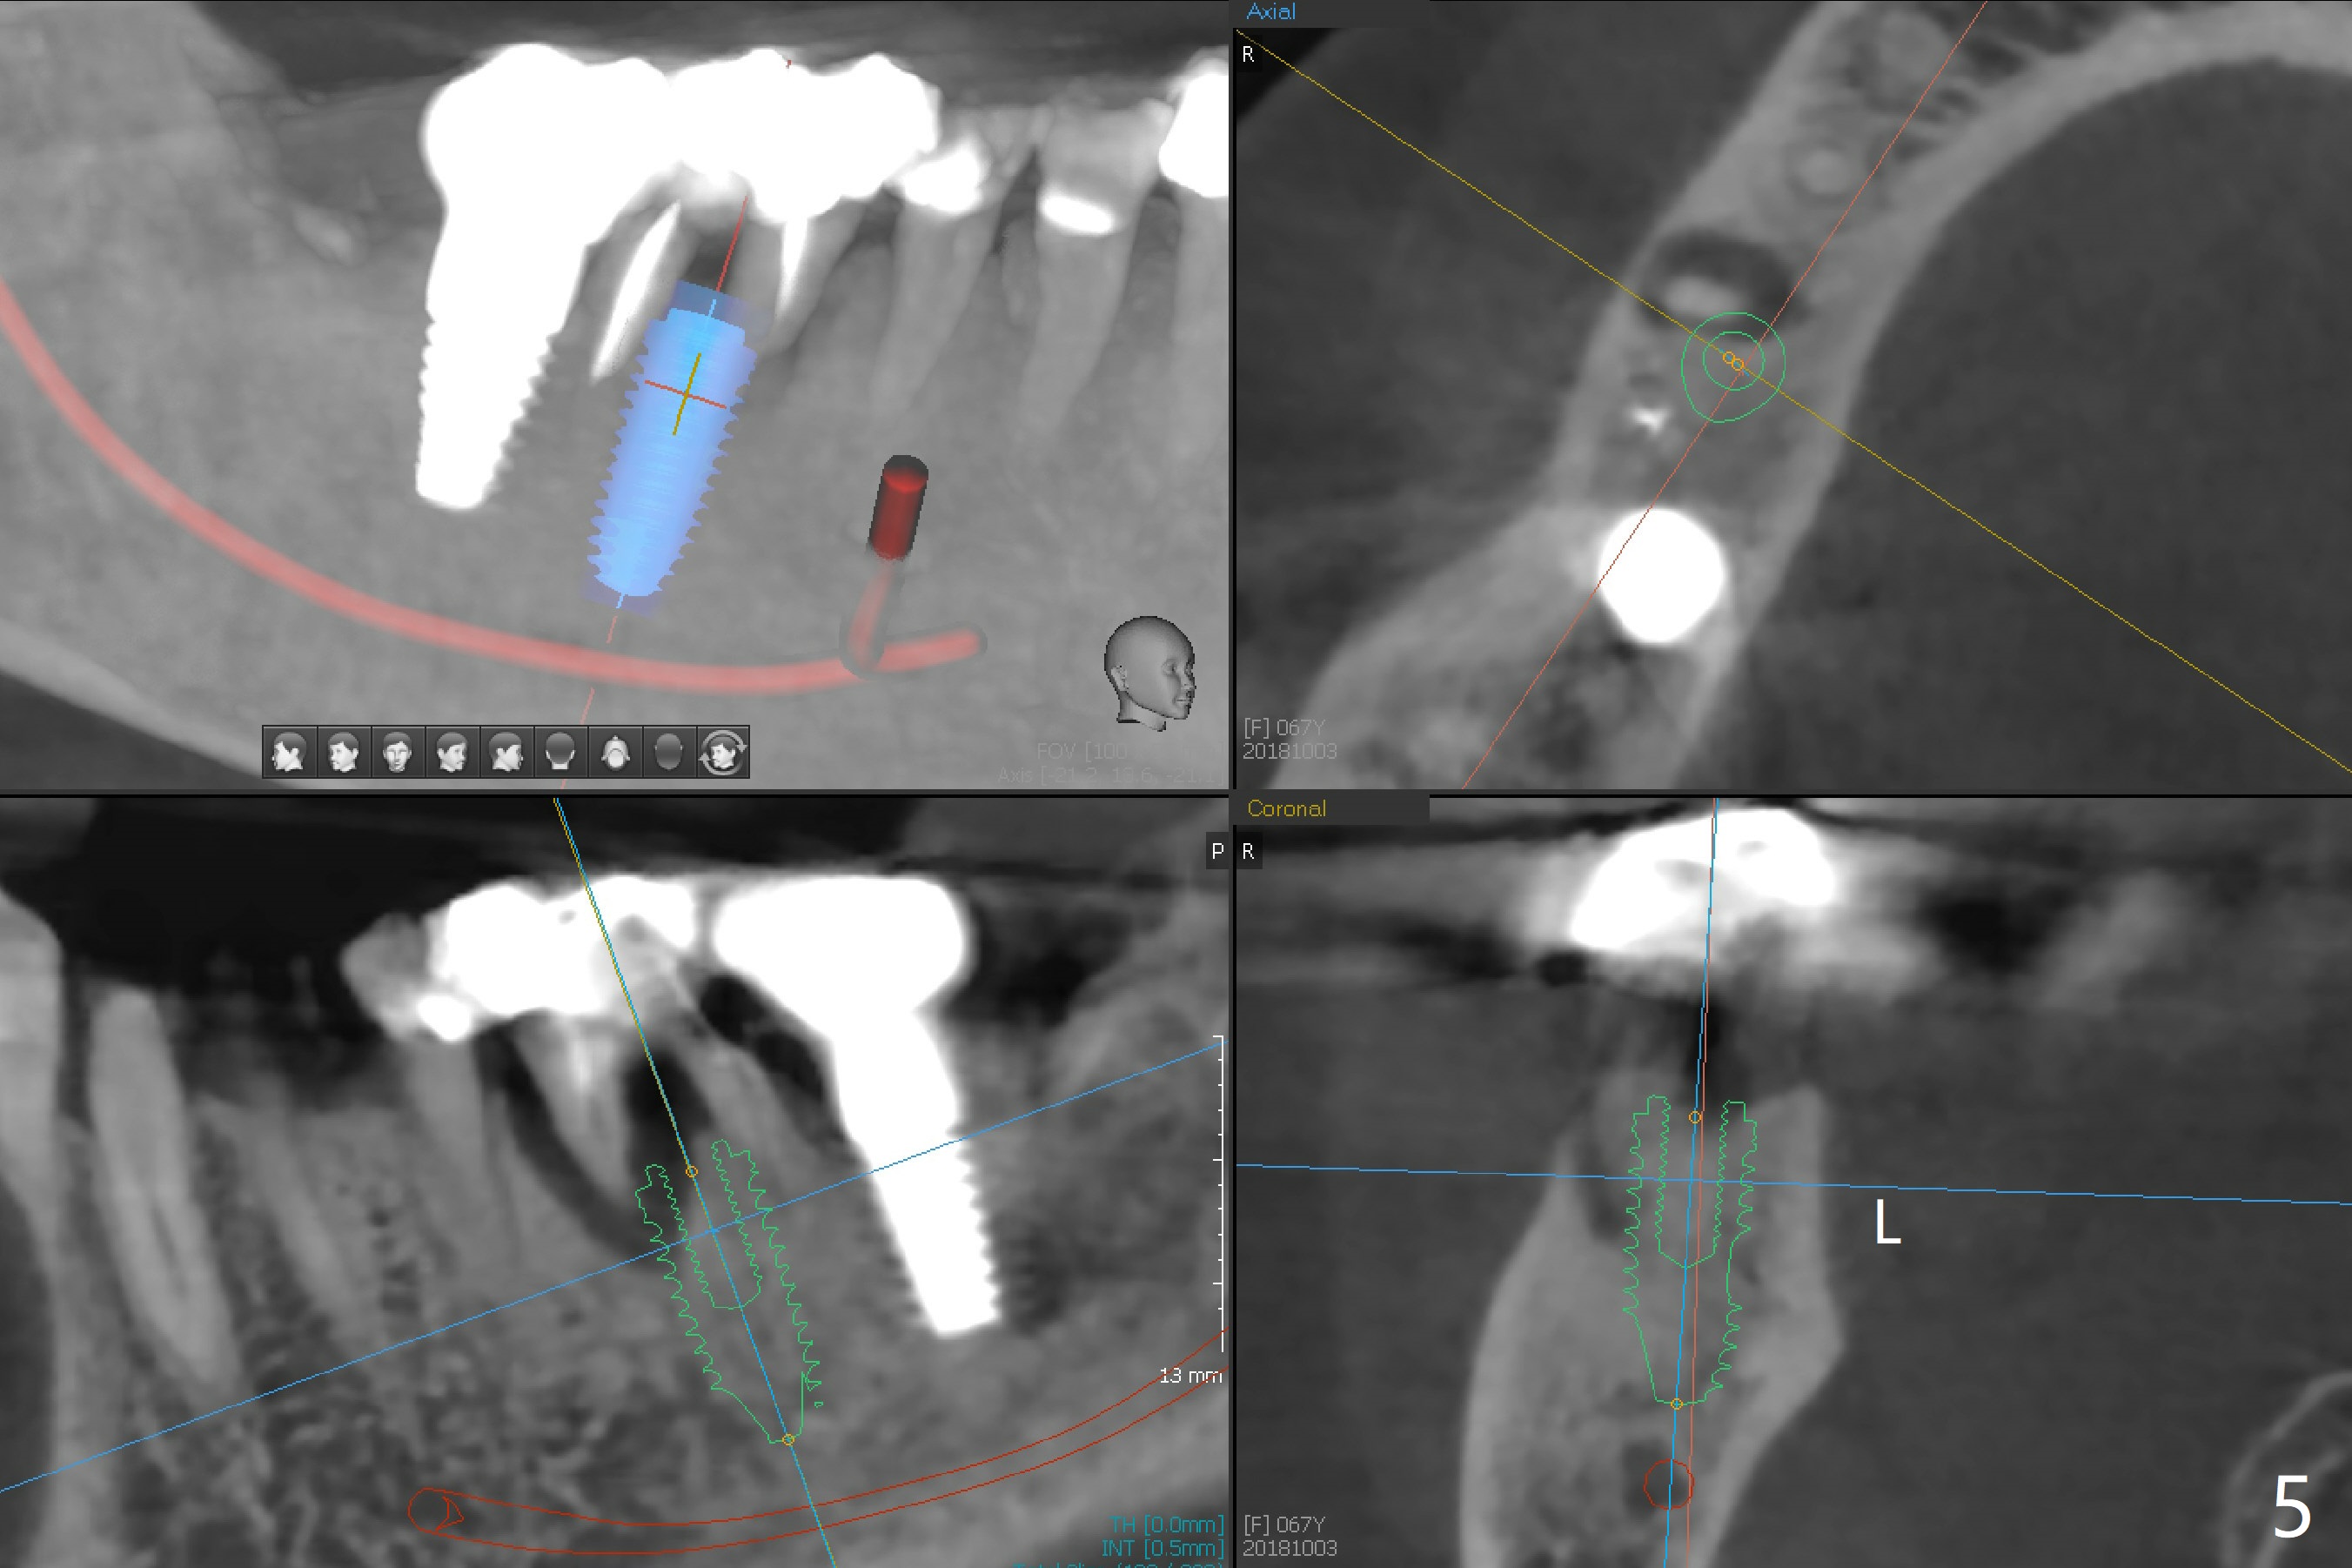

A 67-year-old woman masticates on the right side (Fig.1 (5 years post #30 RCT), as compared to Fig.4,6). One year and 6 months later, there is a fistula mesiobuccal to the tooth #30 (Fig.2 >,4) with mesial root fracture (Fig.3 >). Impression is taken for guide; a 5x11.5 mm implant will be placed slightly distal and lingual to the center of the septum (Fig.5).